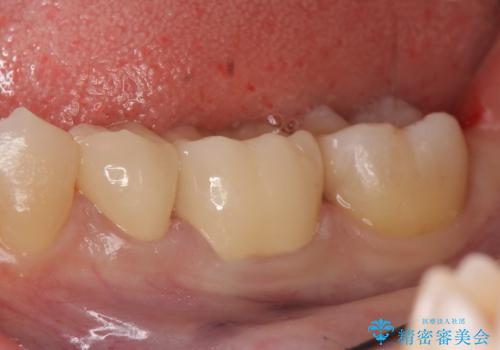

- 左下奥歯の銀歯が気になると来院された方の症例です。

左下7はセラミックインレーによる修復を行い、左下5、6はオールセラミッククラウンによる補綴を行いました。

オールセラミッククラウンについて

今回用いたオールセラミッククラウンはジルコニアフレームという白い素材の上にセラミックを盛っているため、審美性が非常に高いのが特徴です。

また、ジルコニアは人工ダイヤモンドの材料にも使われているほど高い強度を持っており、そのためオールセラミッククラウンは審美性だけでなく、奥歯やブリッジの補綴も可能とするクラウンです。